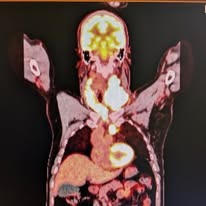

“I think it's time to go to the emergency room,” Sunny said. But they couldn't do anything for me, not in Fort Bragg. I waited in the Fort Bragg ER for 10 hours while they took two CAT scans. But there was no one who could act on the information. No one to draw a sample from that splattered egg on my neck.

A tiny part of me thought “cancer” when I saw the swelling, and my experience with COVID has taught me to take that intuition seriously. And what I knew, in those moments before I had detailed results, is that an infection would be localized. These growths seemed to be everywhere. Which means that it was likely lymphoma.

The more answers we were learning about this disease, though, the more we’ve liked them. If you have to have a cancer, the saying goes, have lymphoma. This is lymphoma, which means it will respond to chemo, and shouldn’t require more intensive intervention. It’s a diffuse large B-cell type lymphoma, which is the reason it took over my neck in the space of a week – but also means it really responds to chemo, and fades quickly. The goal for this cancer is not remission, our oncologist said. It’s a cure.

There’s a long way to go, and some uncertainties. I have a lacy web of numbness on the left side of my face, everywhere served by cranial nerve number 7. Lymphoma doesn’t explain it, so they’re looking into extra white blood cell types showing up in my spinal column. The fear is that cancer cells have traveled into my brain, which would take this up to a Stage IV cancer. Sunny and I tend to take the Occam’s Razor approach: there’s all sorts of swelling going through my shoulders to my face. It wouldn’t take much to block that nerve.